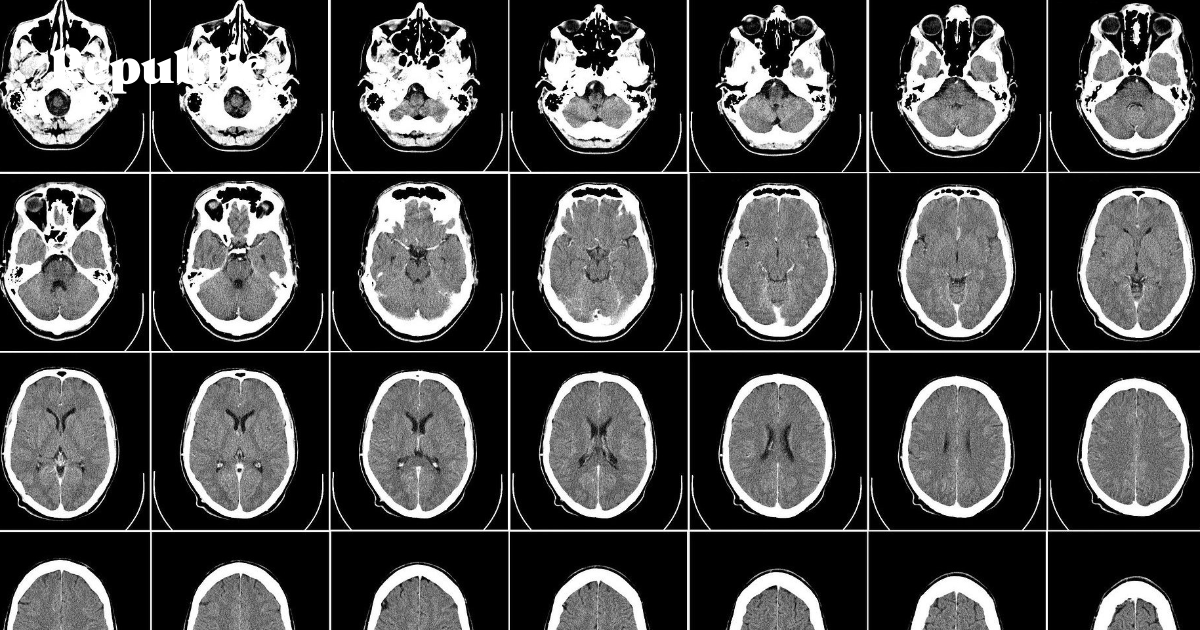

Теперь же три крупных медицинских центра в США готовятся опубликовать данные об этом феномене. У них достаточно скромная выборка, но тем не менее с их помощью можно узнать новую информацию о том, что вирус делает с нашими телами. Например, то, что у сравнительно молодых (и в остальном – здоровых) пациентов с коронавирусом встречается закупорка крупных кровеносных сосудов (large vessel occlusion, LVO), в результате которой могут погибнуть области мозга, ответственные за движение, речь и принятие решений.